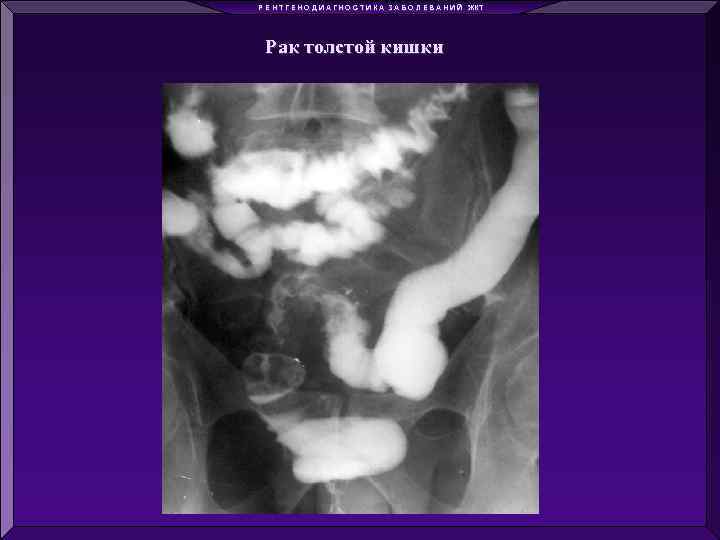

Р Е Н Т Г Е Н О Д И А Г Н О С Т И К А З А Б О Л Е В А Н И Й ЖКТ Рак толстой кишки

Р Е Н Т Г Е Н О Д И А Г Н О С Т И К А З А Б О Л Е В А Н И Й ЖКТ Рак толстой кишки

Р Е Н Т Г Е Н О Д И А Г Н О С Т И К А З А Б О Л Е В А Н И Й ЖКТ Рак толстой кишки

Р Е Н Т Г Е Н О Д И А Г Н О С Т И К А З А Б О Л Е В А Н И Й ЖКТ Рак толстой кишки

Р Е Н Т Г Е Н О Д И А Г Н О С Т И К А З А Б О Л Е В А Н И Й ЖКТ Рак толстой кишки

Р Е Н Т Г Е Н О Д И А Г Н О С Т И К А З А Б О Л Е В А Н И Й ЖКТ Рак толстой кишки